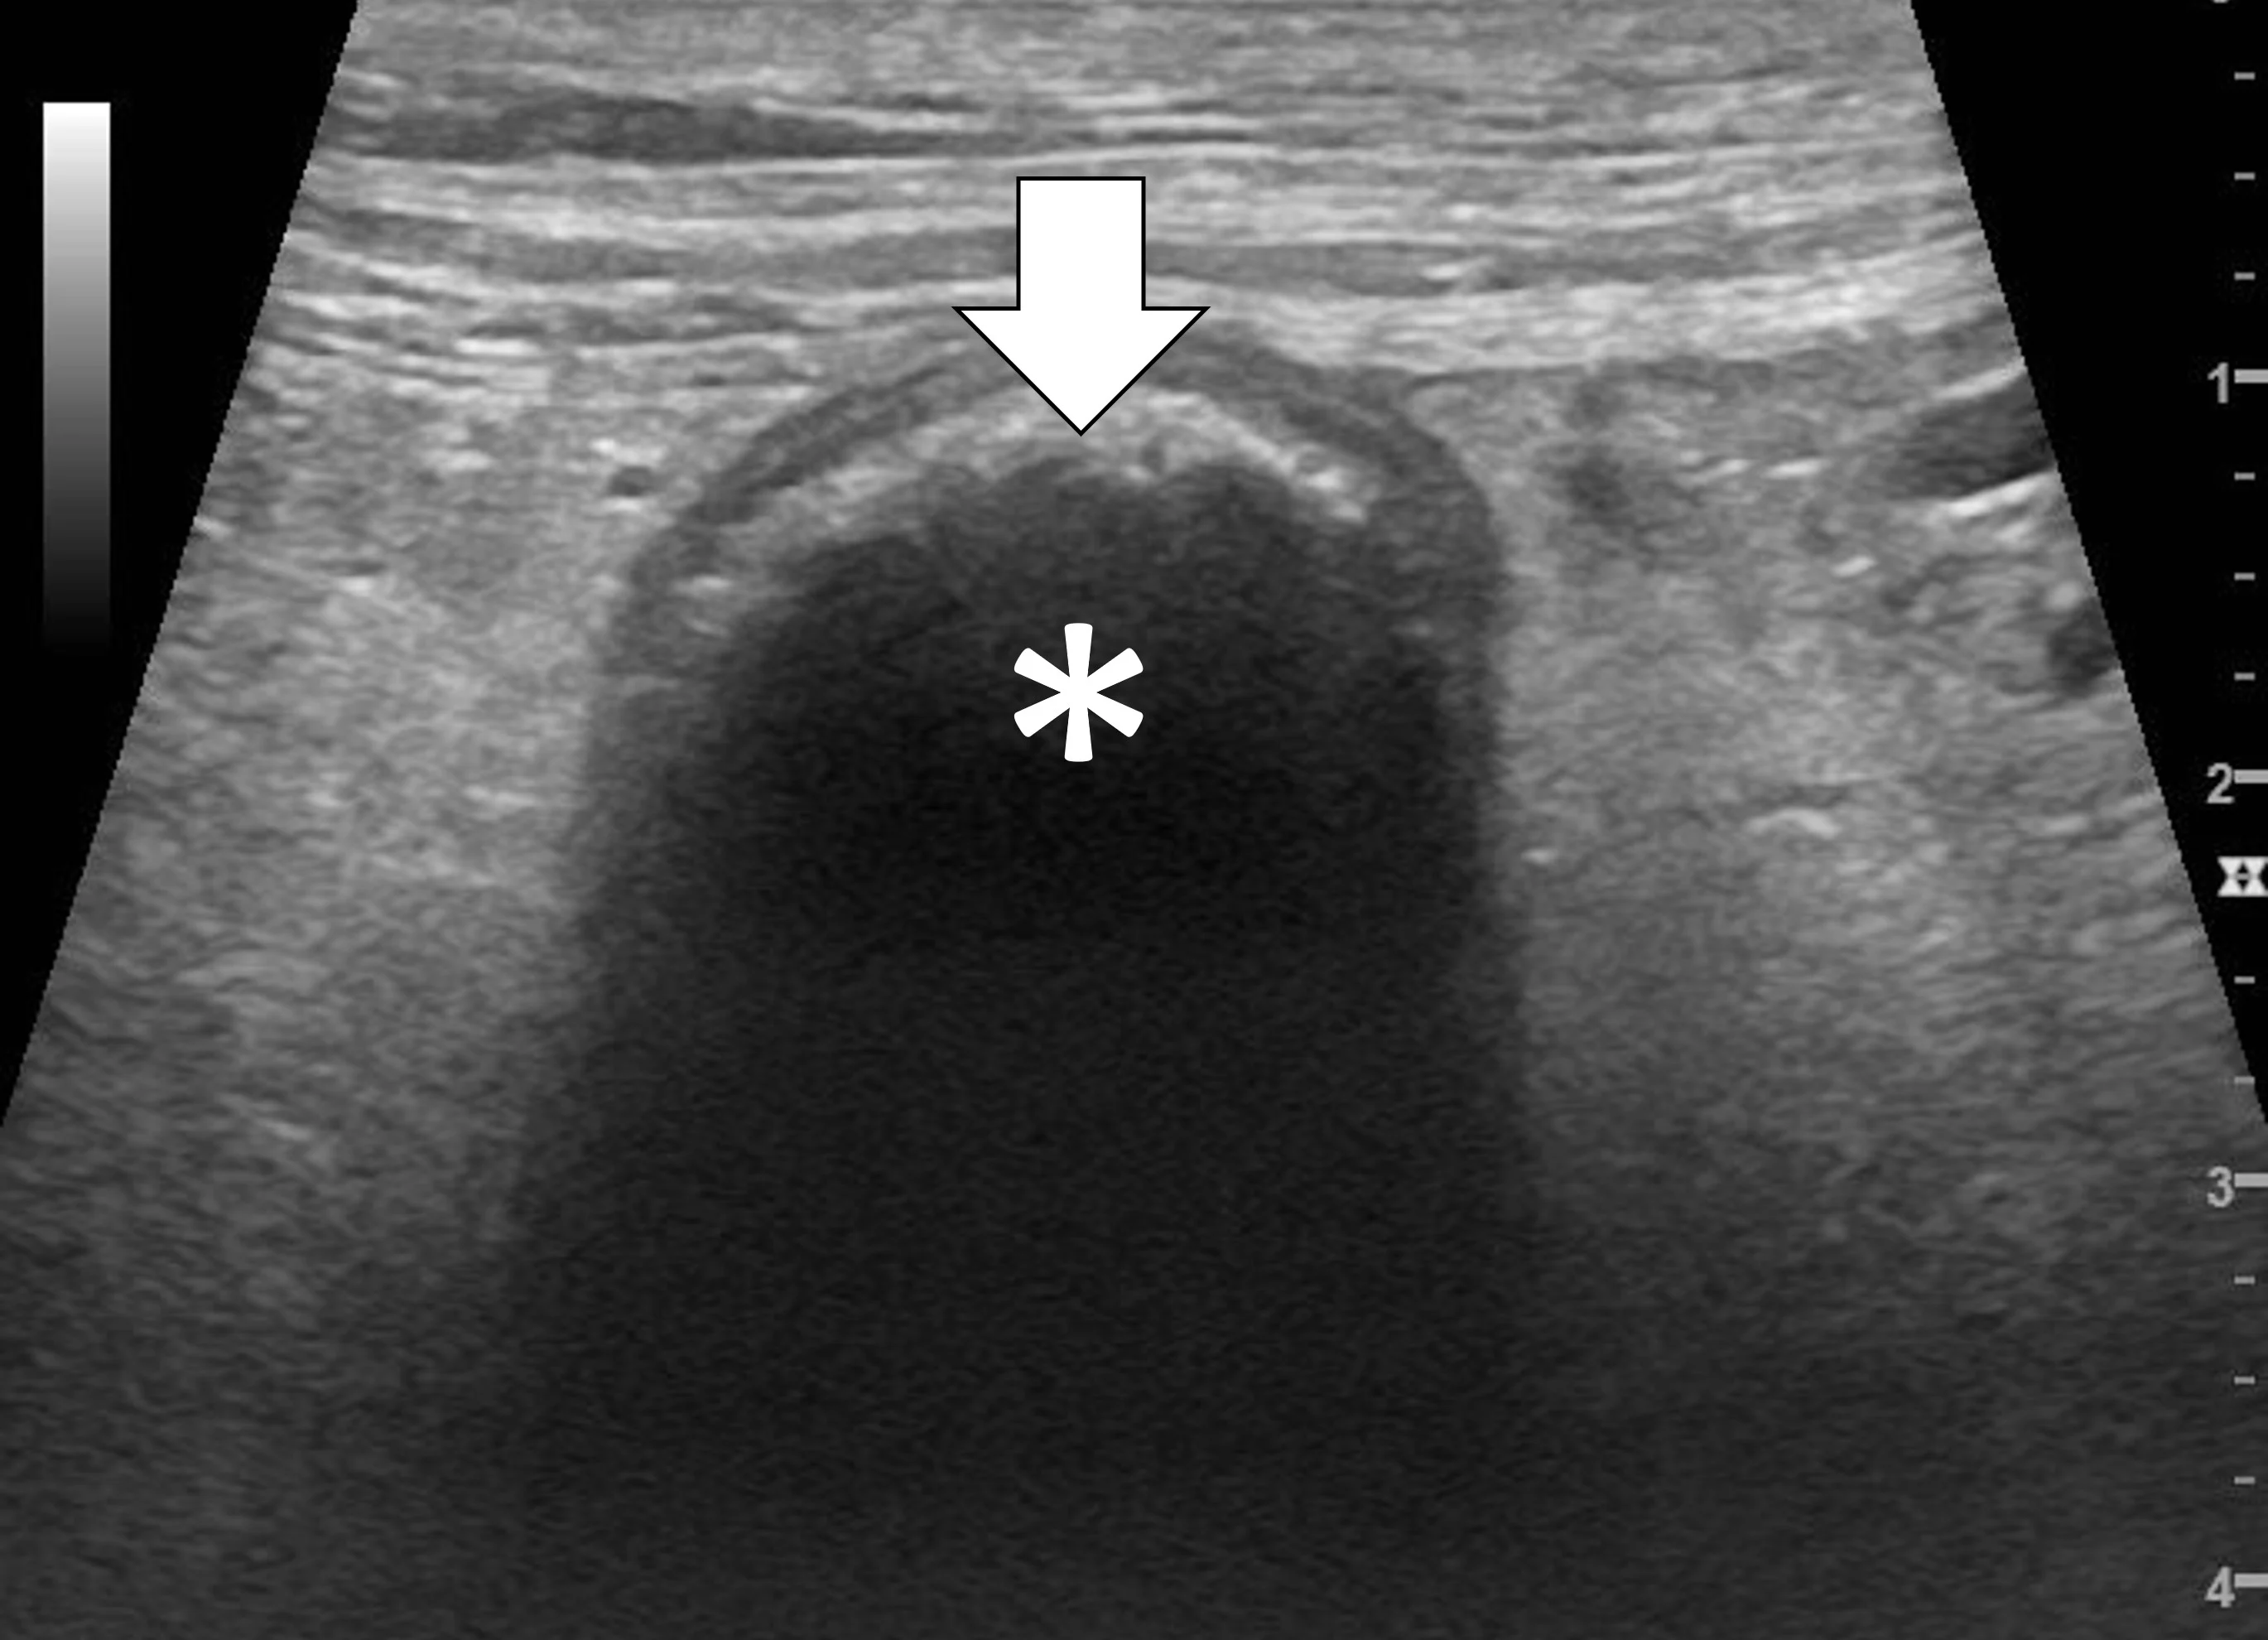

The majority of GI foreign bodies are denser than surrounding soft tissues and fluid. Most of the ultrasonography beam is reflected when there is a sudden change in tissue density (more accurately, acoustic impedance), and further echoes deep to that surface are not produced. The resultant image is a bright hyperechoic line that contours to the shape of the foreign body (eg, plastic toys, rubber balls, cloth, bones, metal), with variable distal acoustic shadowing (Figure 1).9-12 Foreign bodies filled with gas have a similar appearing hyperechoic surface but cause a reverberation artifact (ie, dirty shadow). The entire foreign body will be visible if it is hollow and filled with fluid or has a density similar to soft tissue. Locating foreign bodies can be challenging when only the surface is visualized, but ultrasonography can help detect other changes associated with pyloric outflow, small intestinal mechanical, and linear foreign body obstructions.

Abdominal ultrasound of a 6-year-old neutered male crossbreed dog with a surgically confirmed foreign body (cloth) in the duodenum. The cloth is seen as a hyperechoic curvilinear structure (arrow) that causes a distal acoustic shadow (asterisk).